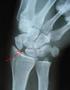

2 DRUJ 1. Piano key sign- for instability = ballottement of ulnar head, (prominence of ulna) 2. squeeze and turn test- o The examiner stabilises the patient's forearm with one hand while with the other hand, he grasps the patient's hand as if for a vigorous handshake. When the patient resists forced passive rotation, or when there is active rotation against resistance, pain usually is elicited. If the pain is caused by compressing the ulna against the radius, it is mostly suggestive of chondromalacia. Ulnar impingement test- For TFCC - shake hands with patient; ulnar deviate wrist whilst rotating the forearm. Pain = positive. CARPAL INSTABILITY TESTS A. Scapholunate instability 1.scapholunate ballotment o Using both index fingers and both thumbs, stabilise the lunate between thumb and index finger of one hand and the scaphoid between the thumb and index finger of the other; the scaphoid pushed in a volar to dorsal direction; discomfort in this area suggests the possibility of injury to the Scapholunate Ligament (SLL). 2. Kirk Watson's scaphoid shift test- Scapholunate Ballotment Test o Examiner opposite patient, both elbows on table as if arm wrestling ipsilateral arms. Examiners thumb on scaphoid tubercle, index finger on scapholunate ligament to palpate clunk. SLL initiates scaphoid flexion on radial deviation of wrist. Completion of flexion of scaphoid caused by pressure from surrounding bones. o Normal- can feel scaphoid flexing in radial deviation, thumb pushed away o SLL injury- pressure of examiner's thumb prevents initiation of flexion of scaphoid, then Clunk occurs on sudden pressure from bones. Patient may withdraw hand with pain 'apprehension test' o Must compare to opposite wrist. o N.B. 20 % of normal people have positive test o [Watson HK, Ashmead D4, Makhlouf MV: Examination of the scaphoid. J Hand Surg Am. 1988; 13: ]

3 Kirk-Watson Test Original Description by Watson: 'The patient is approached by the examiner as if to engage in arm wrestling, face to face across a table with diagonally opposed hands raised (right to right or left to left) and elbows resting on the surface in between. With the patient's forearm slightly pronated, the examiner grasps the wrist from the radial side, placing his thumb on the scaphoid tuberosity (as if pushing a button to open a car door) and wrapping his fingers around the distal radius. The examiner's other hand grasps at the metacarpal level, controlling the wrist position. Starting in ulnar deviation and slight extension, the wrist is moved radially and slightly flexed with constant thumb pressure on the scaphoid. This radial deviation causes the scaphoid to flex. The examiners thumb pressure opposes this normal rotation, causing the scaphoid to shift in relation to the other bones of the carpus. This scaphoid shift may be subtle or dramatic. A truly positive test requires both pain on the back of the wrist (not just where you are pressing on the scaphoid tuberosity), and comparison with the opposite wrist is essential.' B. Lunotriquetral instability 1. Lunotriquetral ballotment test (Reagan test) - stabilise the lunate between thumb and index finger of one hand and the triquetrum between the thumb and index finger of the other;the pisiform and triquetrum are pushed in a volar to dorsal direction; discomfort in this area suggests the possibility of injury to lunotriquetral interosseous ligament [Reagan D.S., Linscheid R.L., Dobyns J.H. Lunotriquetral sprains: J Hand Surg Am 1984; 9: ] Reagan Test

August 1st, 2006 Scaphoid Fractures Dr. Christine Walton, PGY 2 Orthopedics Injury Patterns to the Carpal Bones 1) Perilunate pattern injuries 2) Axial pattern injuries 3) Local impaction/avulsion injuries

PERILUNATE AND LUNATE DISLOCATIONS

PERILUNATE AND LUNATE DISLOCATIONS Rebecca Morris Advanced Practitioner Plain Film Reporting March 2011 Perilunate and Lunate dislocations Introduction Definition Anatomy Clinical presentation Mechanism

September 2000 Musculoskeletal Trauma of the Wrist Murat Akalin, Harvard Medical School, Year- IV Gillian Lieberman, MD The Wrist Most common site of injury in entire skeleton Distal radius and ulna fractures